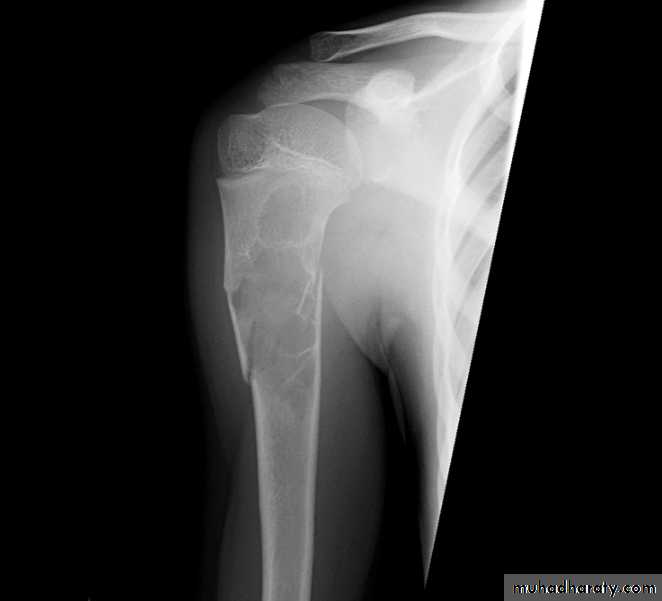

Area of bone destruction or sclerosis with ill-defined margins, wide zone of transition & periosteal reaction with or without cortical destruction & soft tissue swelling.Osteosarcoma :

Age: 5-20-yrs, elderly with Paget's disease.Site: metaphyseal around the knee joint.

Findings:

Lytic

Blastic

Mixed

Poorly defined bony destruction.

Sun ray speculation (periosteal reaction).

Elevation of the periosteum at the margin producing the so called Codman's triangle.

Cortical destruction.

Soft tissue swelling.